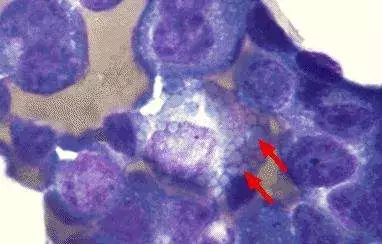

R-S细胞见于Hodgkin’s lymphoma(霍奇金淋巴瘤),是霍奇金淋巴瘤含有的一种体积较大的独特的瘤巨细胞即Reed-Sternberg细胞(简称R-S细胞),典型的R-S细胞是一种直径20~50μm或更大的双核或多核的瘤巨细胞。瘤细胞呈椭圆形,胞浆丰富,稍嗜酸性或嗜碱性,细胞核圆形,呈双叶或多叶状,以致细胞看起来像双核或多核细胞,形态相同状如鹰眼及所谓“镜影”核。染色质粗糙,沿核膜聚集呈块状,核膜厚而清楚。核内有一非常大的,直径与红细胞相当的,嗜酸性的中位核仁,周围有空晕。